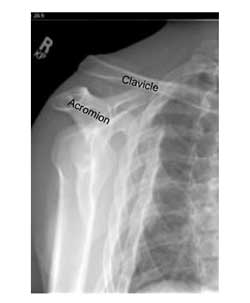

ToggleΟι Κακώσεις της ακρωμιοκλειδικής άρθρωσης συμβαίνουν στην ακρωμιοκλειδική άρθρωση, η οποία εντοπίζεται στην ανατομική περιοχή της ωμικής ζώνης και αποτελεί την σύνδεση μεταξύ του περιφερικού άκρου της κλείδας και της ωμοπλάτης καθώς το ακρώμιο είναι ανατομικό μέρος της ωμοπλάτης και αποτελεί την οστική προεξοχή που γίνεται αισθητή στον ώμο.

Το ακρώμιο συνδέεται με την κλείδα με τη βοήθεια ισχυρών συνδέσμων, τον άνω και τον κάτω ακρωμιοκλειδικό σύνδεσμο και περιέχει έναν διάρθριο χόνδρινο δίσκο που ενεργεί σαν ανάρτηση («ή σαν μαξιλάρι»).